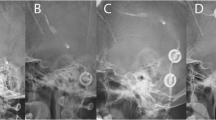

The two remaining CSS were not included in this comparison, as only postoperative MRIs after shunt insertion were available. Figure 1 shows the course of pituitary size in a THG patient before shunting, immediately postoperatively and after 1 and 4 years.

Time course of pituitary size in a child with a medulloblastoma: a preoperatively: note the partial empty sella due to increased intracranial pressure caused by obstructive hydrocephalus. b One day after tumor removal: note the mild increase in pituitary size despite the suboptimal scan quality due to movement artefacts. c 10 months after shunt insertion: note the development of convex pituitary surface. d 3.5 years after shunt insertion: note the further change in the height of the pituitary and slight change in sellar floor morphology